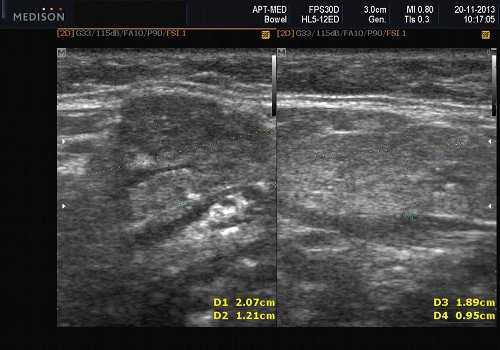

Доброкачественная смешанная опухоль подчелюстной железы при ультразвуковом исследовании

Общие особенности при ультразвуковом исследовании. Лучший диагностический признак: четко очерченная внутрижелезистая опухоль ПЧЖ, которая может выступать на ножке от края железы в поднижнечелюстное пространство (ПЧП), когда она становиться большой

Морфология. Малая плеоморфная аденома: одиночная, цельная, яйцевидная и хорошо разграниченная опухоль. Большая плеоморфная аденома на УЗИ: дольки ± кровоизлияние или некроз ± кальцификация

Результаты ультразвукового исследования слюнной железы

Серошкальное УЗИ. Хорошо выраженная, солидная и гипоэхогенная по сравнению с прилегающей тканью слюны. Однородная внутренняя эхо-структура с задним акустическим усилением. Опухоль имеет несколько тканевых границ и позволяет звуку легко проникать, вызывая улучшение заднего отдела. Большие опухоли могут иметь неоднородные внутренние эхосигналы из-за кровоизлияния и некроза. Гетерогенная плеоморфная аденома может иметь нечеткие границы, имитирующие злокачественную опухоль. Большие опухоли могут иметь дольки и появляться на ножке. Необычный кальциноз при ультразвуковом сканировании наблюдается при давней опухоли. Кожа и подкожные ткани в норме